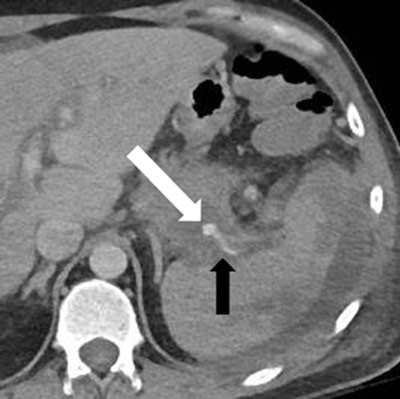

Figure 4a

Enhanced CT, a few days later: recurrent hemorrhage (white arrow) arising retrogradely from the distal splenic artery (black arrow).

Figure 4b

Microcoils embolization of the distal splenic artery (white arrow) through superselective catheterism of the gastroepiploic arteries (thick black arrow); the thin black arrow indicates the previous ostial coiling.